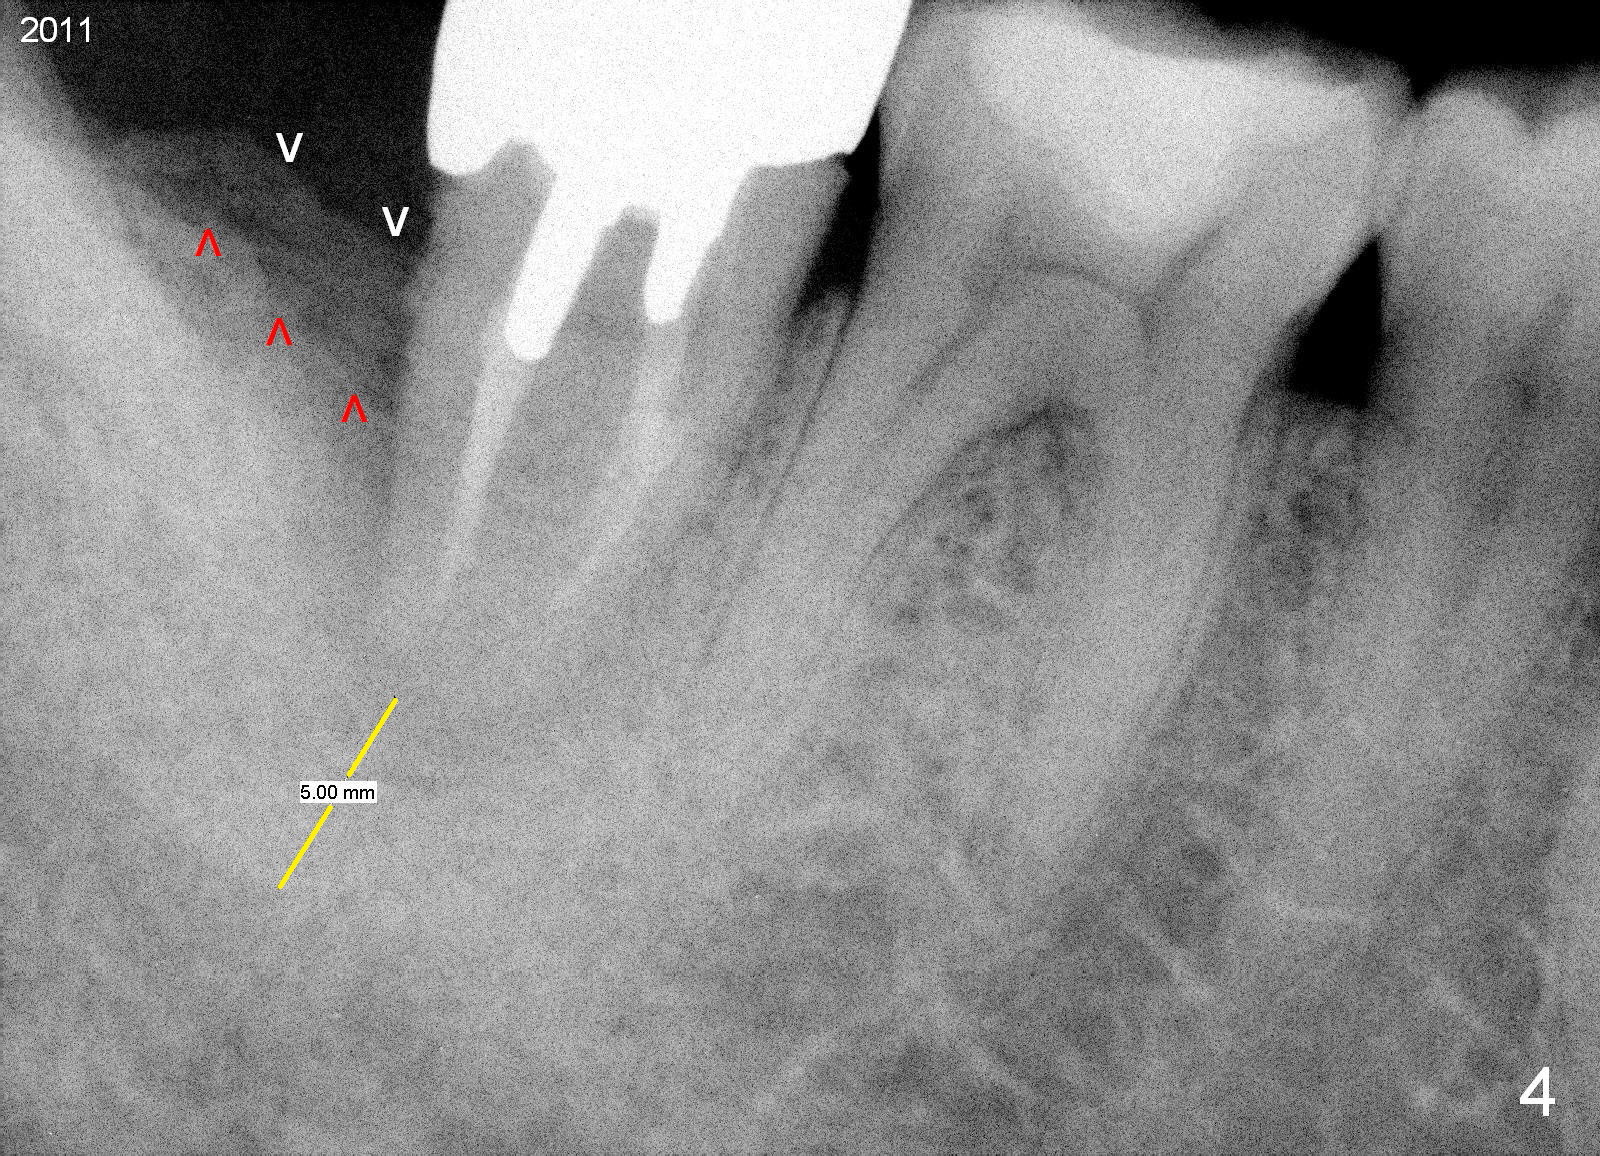

A 44-year-old man has had an asymptomatic distal defect of the tooth #31 for 8 years (Fig.1-5).  Recently there is an acute episode of swelling and pain.  A fistula develops mesiobucally.  Panoramic X-ray films tend to show that the distal defect is deep (Fig.2,5; yellow dashed line: upper border of the Inferior Alveolar Canal).  In addition, the distal defect may be not even buccolingually, as indicated by white and red arrowheads in Fig.3,4.  Following placement of a 6.9x10 mm bone-level implant, a 7.8x4 (4.5) mm cemented abutment is inserted for try in (Fig.6).  When it is fit, it is removed and a cover screw is temporarily placed.  A piece of Osteotape (~10x4 mm) is placed distobuccally or distolingually (depending upon which wall is lower).  A small amount of bone graft is packed between the most coronal portion of the implant and the Osteotape.  The cover screw is then removed and the abutment is re-inserted and tightened by hand.  An immediate provisional is fabricated with well-trimmed margin.  Reline is done if necessary for securely holding bone graft in place.  A new PA is to be taken prior to surgery to determine the extent of the lesion.  Photos are taken to show the mesiobuccal fistula.  Return to Lower Molar Immediate Implant Xin Wei, DDS, PhD, MS 1st edition 04/12/2015, last revision 05/25/2018